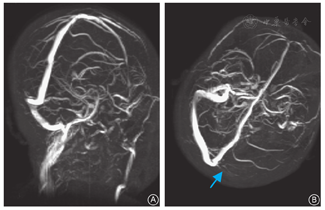

术后第8天晚,患者突发双侧腹股沟区、腘窝至小腿后内侧放射性绞痛,予以杜冷丁肌内注射后缓解。次日膝关节周围轻度胀痛,双下肢无淤血及肿胀,肢端血运良好,考虑功能锻炼引起,继续予以镇痛处理。第11天,血小板计数34.4×109/L。术后第13天,双侧腘窝及小腿胀痛加剧,双下肢皮温稍低,足背动脉搏动减弱。急查双下肢血管彩色超声检查显示双侧腘动脉不全栓塞(图1)。请血管外科会诊,继续低分子肝素治疗,加用盐酸沙格雷酯片(100 mg,3次/d)抗血栓、红外线照射(2次/d)。第14天,患者出现轻微头痛,无恶心、呕吐,未予特殊处理。第16天血小板计数57.4×109/L,继续低分子肝素治疗。当晚患者头痛加剧,伴恶心及喷射状呕吐,颅脑MRI示脑静脉窦栓塞(图2),血压190/100 mmHg,随后出现休克、神志不清、深度昏迷,经抢救无效死亡。